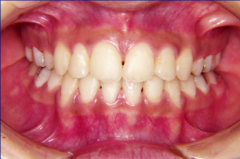

装置装着後